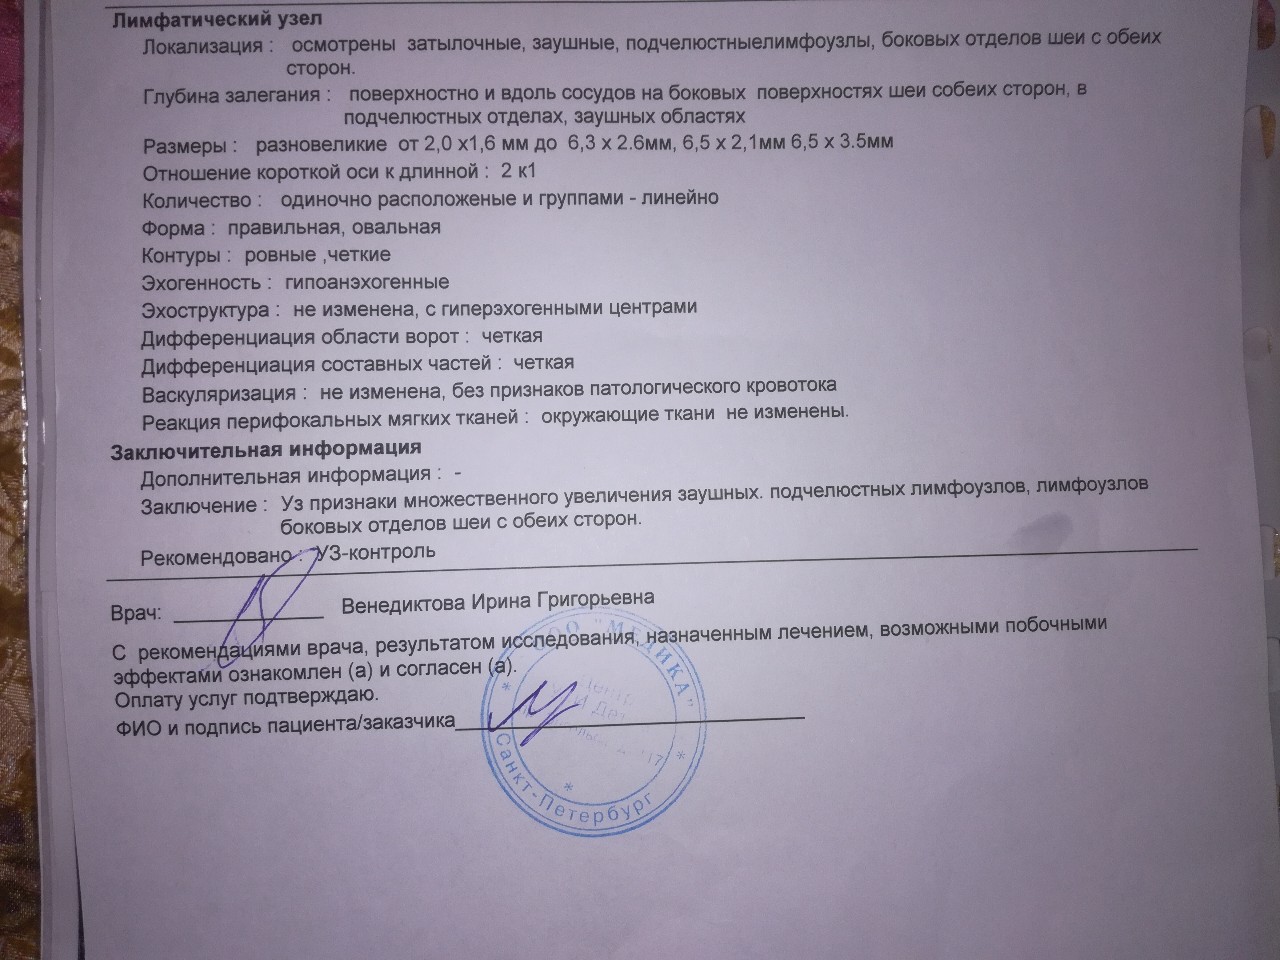

Медицинская визуализация: Признак Кюстнера-Чукалова

Раздел: Необычные решения